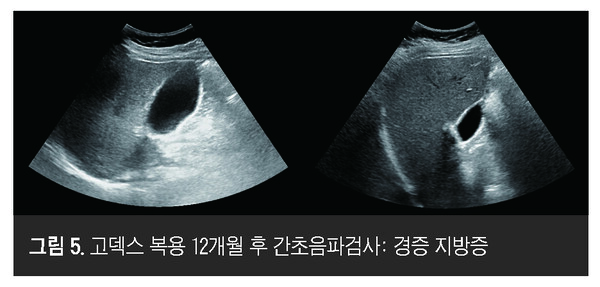

또한 복용 전 시행한 간섬유화 및 순간탄성측정법 검사에서 3단계의 간섬유화 10.3 kPa, 지방 침착 정도를 비교한 CAP 수치 361 dB/m으로 중증 섬유화 및 지방증이 확인됐던 것이<그림 2>, 복용 6개월 후 시행한 순간탄성측정법 검사에서 7.3 kPa, CAP 335 dB/m으로 간섬유화 및 지방증이 호전되는 양상을 보였다<그림 3>. 복용 12개월 후 시행한 검사에서 6.9 kPa, CAP 323 dB/m으로 간섬유화가 정상으로 호전되는 양상을 보였다<그림 4>. 복부초음파에서도 복용 전 확인된 중등증 지방증이 12개월 복용 후 경증 지방증으로 호전된 것을 확인할 수 있었다<그림 5>.

본 증례는 체중 과다 이외의 특이 질환이 없는 MASLD 환자에서 F3 단계로 진행된 섬유화가 확인된 경우이다. GODEX를 12개월간 투여하고 생활 습관 교정을 병행한 결과, 간효소 정상화, 간내 지방 감소(CAP 감소, 초음파상 지방증 호전), 더 나아가 섬유화 지표 호전(10.3 → 6.9 kPa)을 관찰하였다.